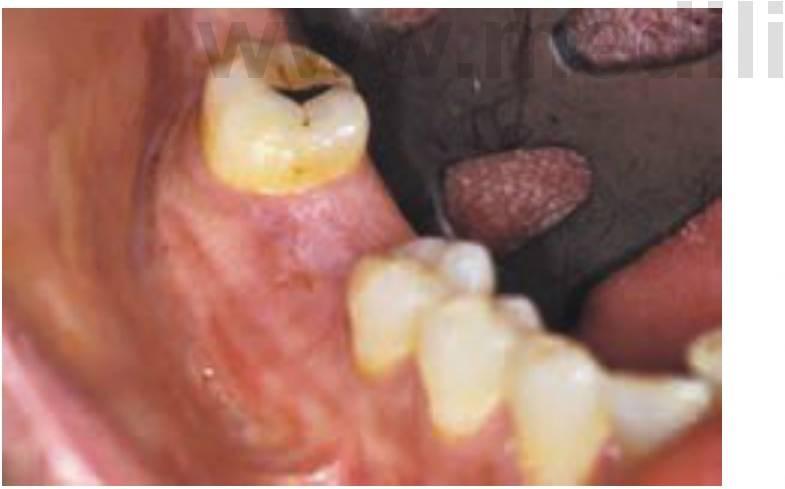

Las regiones posteriores de la boca suelen requerir la sustitución de un solo diente21'23 (fig. 1-5). Los primeros molares son el primer diente permanente en erupcionar en la boca y, desafortunadamente, suelen ser la primera pieza que se pierde por caries dentaria, fracaso de la terapia endodóncica o fractura (normalmente posterior a una endodoncia). Son dientes importantes para el mantenimiento de la forma de la arcada y de los esquemas oclusivos correctos. Adicionalmente, el paciente adulto suele llevar una o más coronas, como consecuencia de reparaciones importantes previas requeridas para reparar la integridad del diente. Los datos sobre la longevidad de las coronas han aportado resultados muy dispares.

Se ha observado que la vida media en el momento de la rotura es de 10 años. Otros datos revelan un rango de entre un 3% de fracaso a los 23 años hasta un fracaso del 20 % a los 3 años. La causa primaria del fracaso de la corona es una caries seguida de una terapia de endodoncia. El diente corre el riesgo de la extracción como resultado de estas complicaciones, que son las causas principales de la pérdida individual de un diente posterior en el adulto (fig. 1-6). Se ha evaluado que una corona de 245 dólares de valor en un paciente de 22 años supondrá un coste a lo largo de la vida del paciente de 12.000 dólares en repararlo/reemplazarlo.

Las consecuencias desfavorables del fracaso de una PPF incluyen la necesidad de reemplazar una prótesis que ha fracasado y la pérdida de un pilar, y la necesidad de pónticos adicionales y pilares dentales en el puente de sustitución. Se pueden perder los pilares dentales de una PPF hasta en un 30 % de los casos en un plazo de 14 años. Se pierden aproxi madamente entre el 8 y el 12% de los pilares dentales que sujetan una PPF en el plazo de los primeros 10 años. El mo tivo más común para la pérdida individual de un diente es el fracaso endodóncico o la fractura del diente (normalmente posterior a un tratamiento endodóncico). Por el hecho de que los pilares dentales requieren una endodoncia, y de que la terapia del canal radicular tenga éxito en el 90% de los casos en el plazo marcado de 8 años, los pilares dentales están más sujetos a sufrir caries cuando se encuentran inmovilizados mediante un póntico intermedio. Las coronas individuales tienen una media de incidencia de caries inferior al 2%; sin embargo, el riesgo de caries en los pilares dentales es del 20%, principalmente porque el área del póntico actúa como reservorio de placa. Una lesión de caries en un margen de la corona puede causar un fallo estructural, incluso siendo posible el tratamiento endodóncico (fig. 1-7).